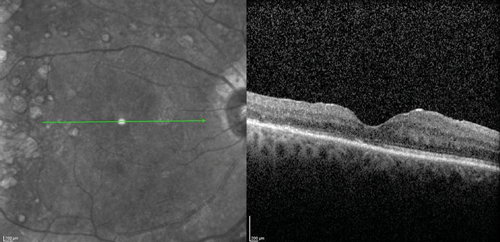

The clinical efficacy and safety of the drug have been also reported in two case reports of vitrectomised eyes with persistent DMO with both cases showing a desirable anatomical outcome. In one case, the authors have suggested that vitrectomy seemed to have enhanced the performance of the implant in-situ and achieved complete DMO resolution [19]. In a recently presented series of 20 post PPV eyes of 18 patients treated with Iluvien, a mean change of BCVA of +9 ETDRS letters (range -6 to +27) as well as mean reduction of CRT by -224µm (-595 to +126) were reported after a mean follow-up period of 201 days (range: 45 to 367 days) (SFO Paris 2016). Further real-life data of Iluvien in vitrectomised eyes with comparable clinical outcomes are awaited with interest. The author’s experience with the drug so far is in-keeping with published cases (Figure 1).

Figure 1 (c).

Figure 1: Case study for management of post-vitrectomy refractory DMO: (a) Pre-vitrectomy; (b) Post-vitrectomy; (c) Post six intravitreal anti-VEGF treatment with sub-optimal response; (d) Post-Iluvien one month. Complete resolution of DMO; (e) Post-Iluvien 10 months. Maintained response to treatment. (Courtesy of Mr David H W Steel - Sunderland Eye Infirmary).